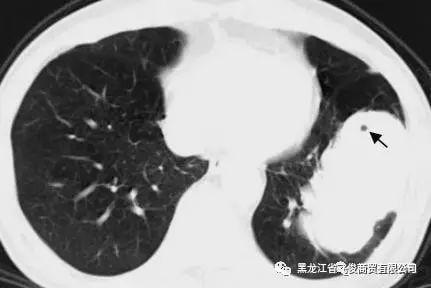

抽烟人肺部x光片图片,抽烟的肺部x光片图片

常吸烟得人身体若有3处疼,肺部8成"百孔千疮",最好戒烟

男子抽烟40年,身体不适去检查,发现肺里有直径25厘米的气泡

不吸烟吸烟感染冠状病毒三个肺部x光照片看完我想戒烟了

抽烟的肺部x光片图片

抽烟肺部图片真实

肺部x光片

肺部x光片怎么看

正常人的肺部ct图片

肺部正常的ct图片

肺癌x光片